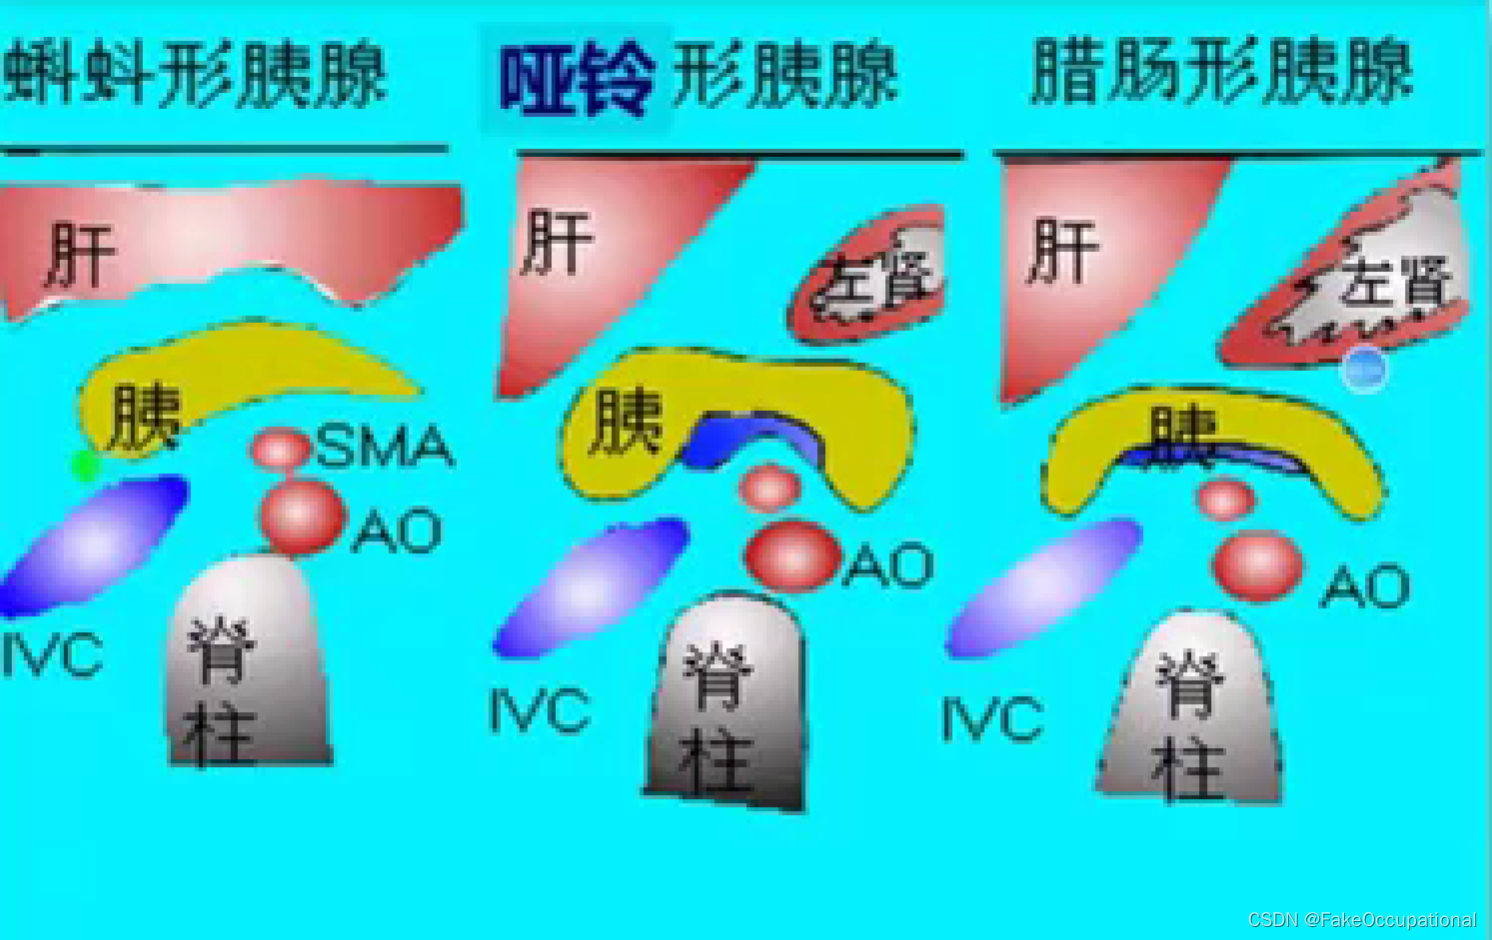

位置: 胰腺的体表投影在脐上5cm-10cm处,位于第一第二腰椎体前方,胰尾直达脾门.形态和分部:分为头、颈、体、尾四部分。大致分为蜂料型(最常见) 、腊肠型、哑铃型,

胰头<2cm,2-2.5cm疑大,22.5cm,肿大。>胰体尾部<1.5cm,1.6-2cm疑大,z2cm,肿大.>蝌料形胰头最大值可达3.5cm,而哑铃形及腊肠形胰尾可

达2.5cm